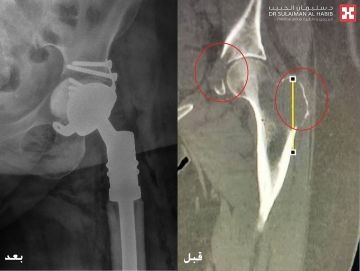

مشيراً إلى أن نتائج الفحوصات كشفت عن وجود ورم خبيث منتشر في عظمة الفخذ والحوض، نتج عنه حدوث تفتت للعظم في تلك المنطقة. مفيداُ بأنه تم تكوين فريق طبي من استشاري جراحة العظام والأورام والتخدير والعناية المركزة، وعقب دراستهم لكامل نتائج الفحوصات، تم اتخاذ القرار بالتدخل الجراحي العاجل ووضع خطة علاجية دقيقة، وذلك للحيلولة دون إصابة المراجعة بمزيد من الأعراض والمضاعفات الحادة، والمتمثلة في كبر حجم الورم وانتشاره في مواضع أخرى بالجسم.

موضحاً بأنه إخضاع المراجعة لجراحة دقيقة استغرقت 4 ساعات متواصلة تحت التخدير العام، وتم فيها استئصال الورم السرطاني وإزالة عظمة الفخذ المتضررة، ومن ثم عمل ترميم للمنطقة المصابة، تبع ذلك زراعة مفصل صناعي من نوع خاص، نقلت بعدها إلى جناح التنويم.